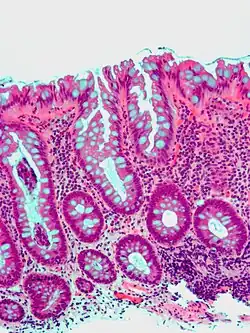

Microvesicular hyperplastic polyp. H&E stain. -